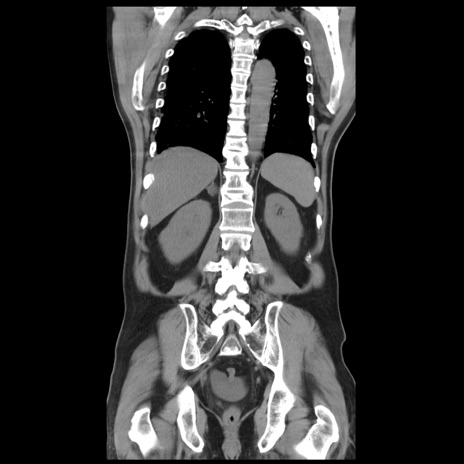

症例20(冠状断像)

【症例】 60歳代男性

【主訴】 腹部膨満、嘔吐

【現病歴】5日前頃より倦怠感を認め食事量減少し4日前の朝嘔吐、食事摂取困難となった。 3日前近医受診し点滴施行され整腸剤などを処方された。 当日他院を受診し、腹部膨満著明、炎症反応の上昇(CRP10.8、WBC11200)あり、紹介受診となる。

【身体所見】 意識JCS1 受け答えがはっきりしないBP 111/57mHg、 P 67bpm、、BT35.2°C、SpO2 97%(RA)、 腹部:膨隆、打診で鼓音あり、全体的に圧痛有り、腸蠕動音(-)、反跳痛ははっきりせず。

【データ】WBC 11400、CRP 14.20